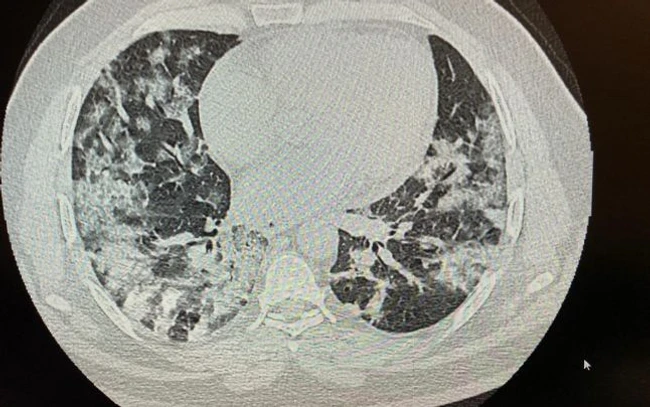

Un caz de azi noapte. Pacient in vârstă de 37 ani, se prezintă la camera de gardă Floreasca pentru sdr subocluziv intestinal şi subfebrilitate. CT-ul lui arată pneumonie interstiţiala. Are 65 saturatie in oxigen. Pentru el definiţia de caz a Institutului de Sănătate Publică nu mai face doi bani. Şi sunt multe asemenea cazuri, cele mai multe atipice, mulţi au doar somnolenţă, astenie, cefalee. Ei merg pe picioare chiar dacă au saturaţia foarte jos, merg la cumpărături, cu transportul public şi nu sunt de rea credinţă. Pur si simplu cred că în lipsa febrei si a tusei nu au această boală. Starea se deteriorează brusc, au nevoie de oxigen si apoi ajung la ATI.

Imaginea CT e atât de sugestivă, saturaţia în oxigen nu mai spun, pacientul va pleca la laşi sau în Medgidia pe locuri eliberate în ATI. Acolo îl aşteaptă Dumnezeu cu mila lui. În Bucuresti nu mai sunt locuri libere. Deci cum facem domnule şi doamnă doctor Bittman şi Chiriac, intră la numărătoare sau nu?